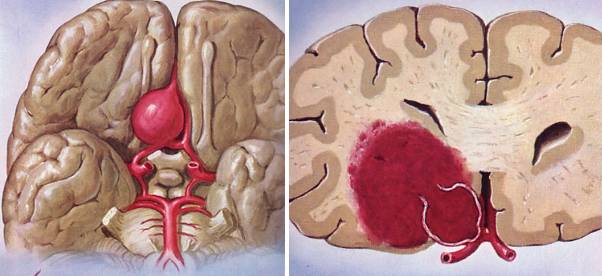

破裂出血的动脉瘤表现为蛛网膜下腔出血、脑内血肿等相应症状。

平扫—般为圆形、葫芦形或条形稍高密度影,动脉瘤壁有钙化时,CT易于显示。如动脉瘤破裂出血则表现为蛛网膜下腔出血,平扫是瘤体不易显示时,需要行CTA扫描。

CTA—囊状动脉瘤表现为起自动脉的囊袋状突起,有蒂(瘤颈)与载瘤动脉相连,轮廓清晰;梭形动脉瘤表现为血管不规则迂曲扩张,无瘤颈。